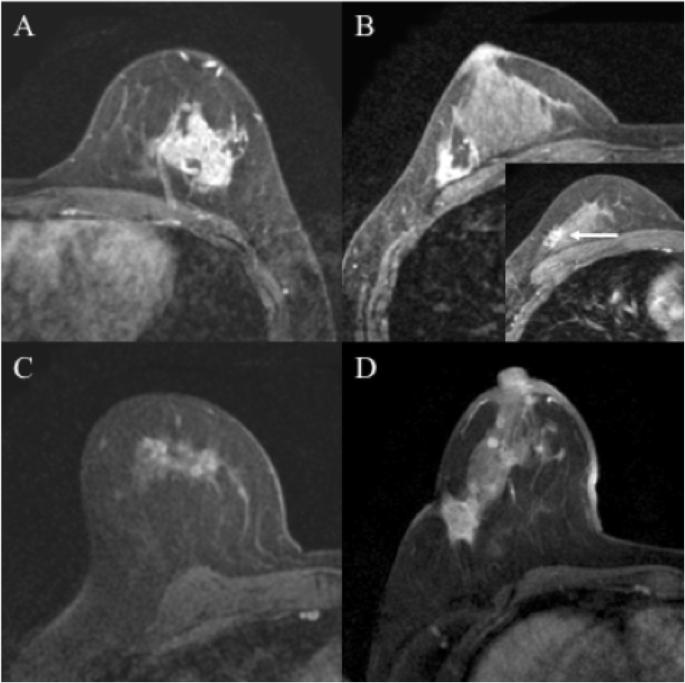

Breast mri is sometimes used in women who already have been diagnosed with breast cancer, to help measure the size of the cancer, look for other tumors in the breast, and to check for tumors in the opposite breast. Magnetic resonance imaging (mri) of the breast — or breast mri — is a test used to detect breast cancer and other abnormalities in the breast. Sometimes changes can look like cancer on an mri scan when they are not. Imaging and lobular breast cancer. A breast mri usually is performed after you have a biopsy that's. For more than half of women who develop stage iv breast cancer, the bones are the first site of metastasis. Recent research has found that mri can locate some small breast lesions sometimes missed by mammography. Tumor size is an important factor in breast cancer staging, and it can affect a person's treatment options and outlook. A waiver of informed consent A sudden, noticeable new pain is the most common symptom of cancer that has spread to the bone. An mri for a breast cancer evaluation is currently the most common reason to have a breast mri. Your doctor may recommend a breast mri for the following: On a breast mri, the contrast tends to become more concentrated in areas of cancer growth, showing up as white areas on an otherwise dark background.

Rapid Breast Mri Could Save Thousands From Cancer Regional Medical Imaging from www.rmipc.net A mri exam helps doctors measure the extent of the cancer, look for other cancer or abnormal tissue in the breast, and monitor for breast cancer after treatment. 69% of breast cancer detected on mri are smaller than 1 cm, the mean size is about 0.8 mm, this earlier detection leads to downstage average cancer and improves breast cancer‐specific survival. Magnetic resonance imaging (mri) of the breast uses a powerful magnetic field, radio waves and a computer to produce detailed pictures of the structures within the breast. A waiver of informed consent Mri of the breast is also considered the modality of choice for detecting breast cancer in patients who have undergone free silicone injections. Indications for breast mri in the patient with newly diagnosed breast cancer. For more than half of women who develop stage iv breast cancer, the bones are the first site of metastasis. On a breast mri, the contrast tends to become more concentrated in areas of cancer growth, showing up as white areas on an otherwise dark background.

However, mri has demonstrated superiority in the evaluation of breast cancer recurrence in the conserved breast following surgery. This is why we ask questions about menstrual cycle and hormone therapies prior to your study. Lobular breast cancer can be more difficult to see on imaging and scans. Mri offers a very detailed picture of breast tissue, but it can also turn up a lot of false positives —suspicious results that prove, later, not to be cancer. A sudden, noticeable new pain is the most common symptom of cancer that has spread to the bone. Need to have physical exam, mammogram, and ultrasound as needed. Some benign conditions such as fibrocystic disease can look like cancer. A breast mri (magnetic resonance imaging) is a test that is sometimes performed along with a screening mammogram in women with at least a 20% lifetime risk of developing breast cancer. 69% of breast cancer detected on mri are smaller than 1 cm, the mean size is about 0.8 mm, this earlier detection leads to downstage average cancer and improves breast cancer‐specific survival. Breast mri images are combined, using a computer, to create detailed pictures. A spiculated breast mass, which has spikes extending out from the main mass, is often highly suggestive of cancer. They might be at higher risk due to having family members with cancer or because they have certain gene abnormalities (mutations). A breast mri scan might also be used to assess the size of the cancer to check which kind of surgery is possible.